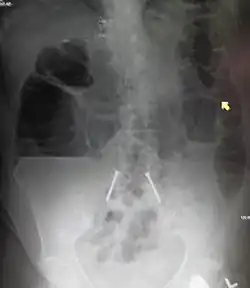

Causes of bowel obstruction include adhesions, hernias, volvulus, endometriosis, inflammatory bowel disease, appendicitis, tumors, diverticulitis, ischemic bowel, tuberculosis and intussusception.[1][2] Small bowel obstructions are most often due to adhesions and hernias while large bowel obstructions are most often due to tumors and volvulus.[1][2] The diagnosis may be made on plain X-rays; however, CT scan is more accurate.[1] Ultrasound or MRI may help in the diagnosis of children or pregnant women.[1]

Radiological signs of bowel obstruction include bowel distension (small bowel loops dilated >3 cm) and the presence of multiple (more than 2) air-fluid levels on supine and erect abdominal radiographs.[16] Ultrasounds may be as useful as CT scanning to make the diagnosis.[17]

Contrast enema or small bowel series or CT scan can be used to define the level of obstruction, whether the obstruction is partial or complete, and to help define the cause of the obstruction. The appearance of water-soluble contrast in the cecum on an abdominal radiograph within 24 hours of it being given by mouth predicts resolution of an adhesive small bowel obstruction with sensitivity of 97% and specificity of 96%.[18]